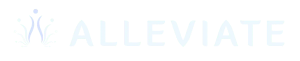

Paraspinal Muscles (Most Commonly Involved)

Muscles

- Erector spinae group (iliocostalis, longissimus, spinalis)

- Multifidus

Role

- Maintain upright posture

- Stabilize each lumbar segment

How they cause right-sided pain

- Muscle strain from bending, lifting, or twisting

- Chronic spasm due to poor posture or disc/facet irritation

Pain pattern

- Localized pain on the right side of the lower back

- Worse with movement, better with rest

- Tenderness and stiffness

Clinical note: Multifidus atrophy is commonly seen in chronic unilateral low back pain.

Quadratus Lumborum (QL) – A Major Culprit

Muscle

- Quadratus lumborum

Role

- Stabilizes pelvis

- Controls side bending of the spine

Why it causes right-sided pain

- Prolonged sitting

- Leg length discrepancy

- Sacroiliac joint dysfunction

Pain pattern

- Deep aching pain on one side (right)

- Pain increases with standing, walking, or side bending

- Referred pain to buttock or hip

Frequently misdiagnosed as kidney pain

Muscle Involvement by Condition (Quick Clinical Mapping)

Condition | Muscles Commonly Involved |

|---|---|

Muscle strain | Erector spinae, multifidus |

Facet joint arthritis | Multifidus, erector spinae (secondary spasm) |

Sacroiliac joint dysfunction | Quadratus lumborum, gluteus medius |

Piriformis syndrome | Piriformis, gluteus maximus |

Disc bulge / sciatica | Paraspinals, piriformis |

Postural pain | Iliopsoas, QL, paraspinals |